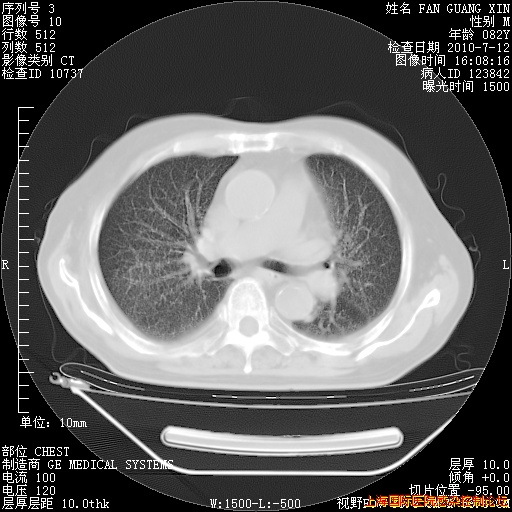

补发6月12日肺部CT肺窗

6月12日肺窗